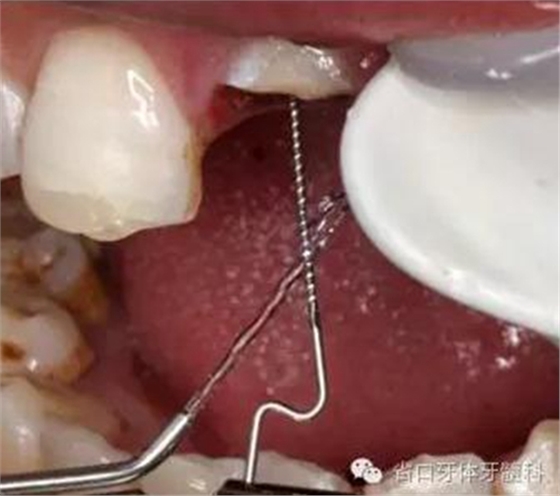

圖9. 腭側(cè)電刀切齦止血、暴露斷面,殘根斷面磷酸酸蝕

圖12. 超聲蕩洗纖維樁道

圖13. 纖維樁及斷冠粘接固定